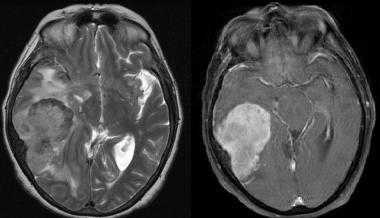

А: на Т1-взвешенном МР-изображении отмечается солидное образование, характеризующееся изоинтенсивностью по отношению к твердой мозговой оболочке, инвазией в кость и сдавлением теменных зон коры.

В: На Т1-взвешенном МР-изображении с контрастным усилением видна частично контрастируемая опухоль.

С: На корональном Т2-взвешенном изображении видно изоинтенсивное образование, что соответствует плотной ткани. Такая картина характерна для фибробластных менингиом.

D : На Т1-взвешенном МР-изображении с контрастным усилением визуализируется гиперинтенсивное образование внутри мозгового вещества кости.